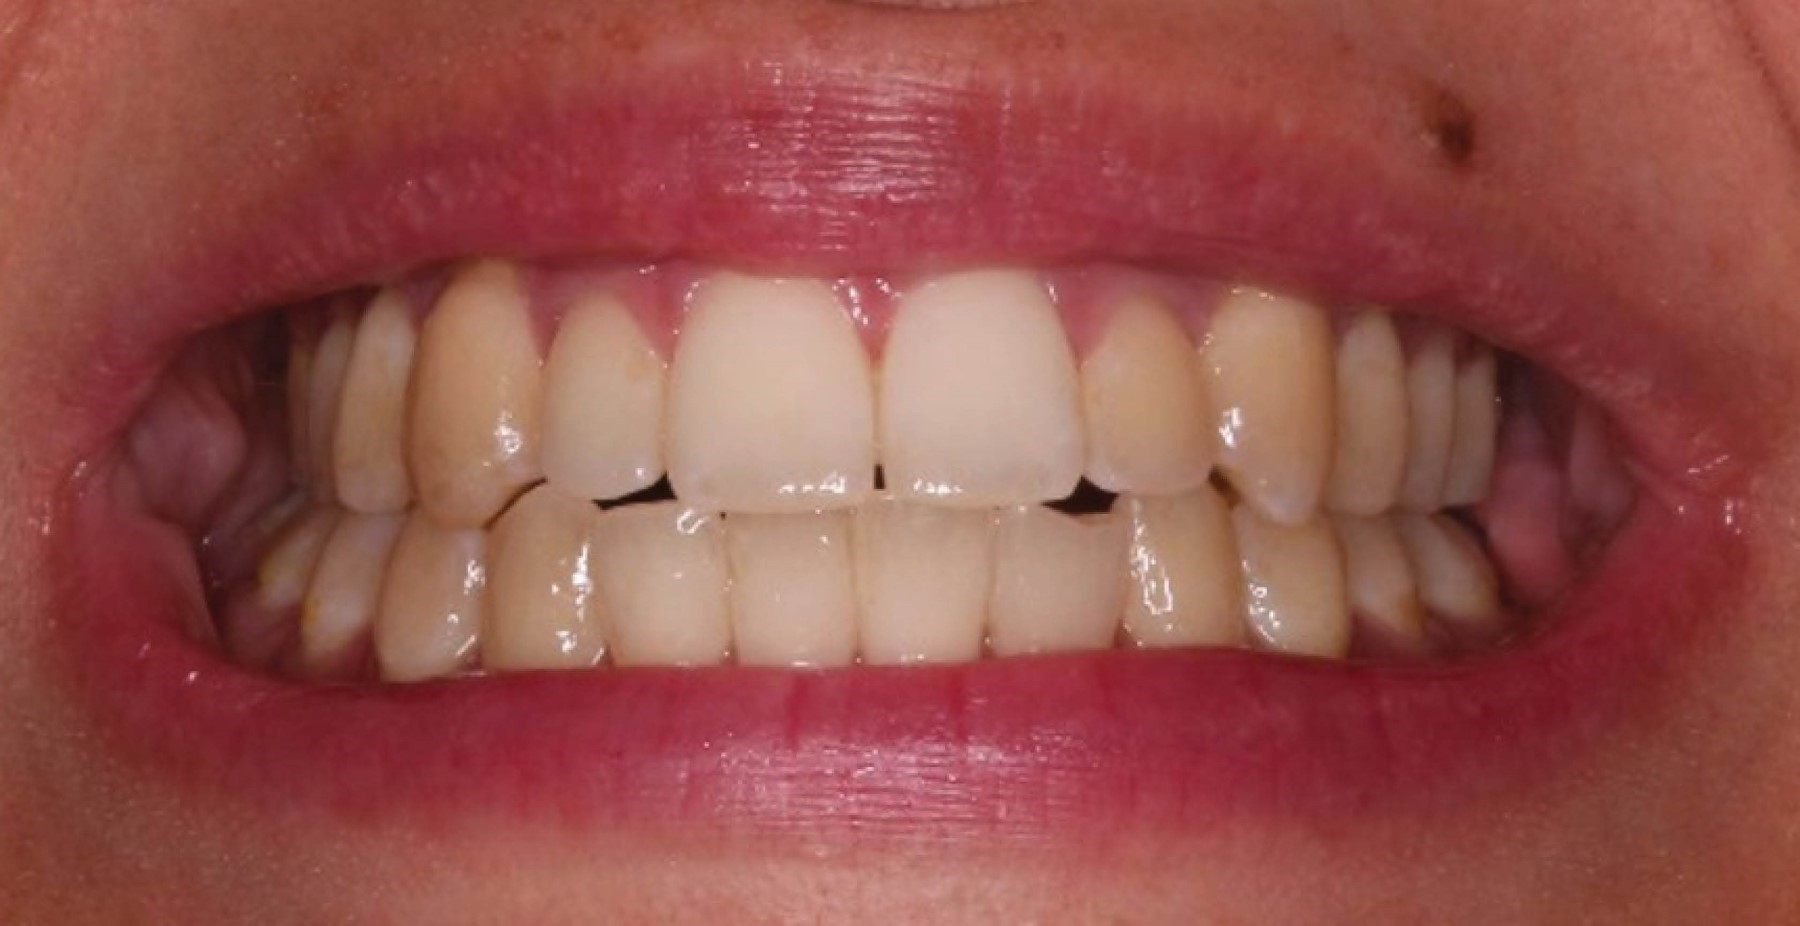

Este enfoque quirúrgico integral buscó corregir la maloclusión y las deformidades esqueléticas (Figura 4), mejorando la proyección mandibular y aumentando el diámetro de la vía aérea (Figura 5), con el fin de lograr estabilidad articular y oclusal y de restituir la estética y la funcionalidad (Figuras 6 y 7).

Figura 6